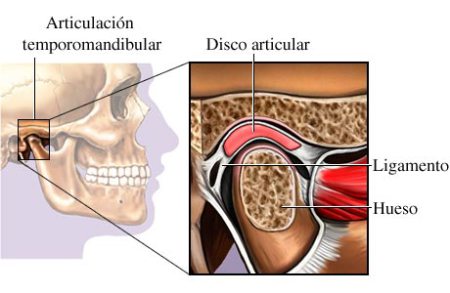

Patología articular

La articulación témporo-mandibular (ATM) es la estructura anatómica encargada de relacionar ambos maxilares. Integrada por el hueso temporal, el cóndilo mandibular y el disco articular, que se interpone entre ambos, guía los movimientos de apertura y cierre bucal, así como los movimientos de lateralidad durante los ciclos de masticación y el habla. Se diferencian en ella dos compartimentos: el superior, entre el hueso temporal y el disco articular, en el que se realiza el movimiento de traslación y un compartimento inferior, entre el disco y el cóndilo mandibular, en el que se realiza el movimiento de rotación. Los diferentes movimientos, así como la limitación de los mismos vendrán determinados por la acción de diversos músculos y ligamentos que participan de la articulación.

Estructura facial y ATM

ATM sana

ATM sana